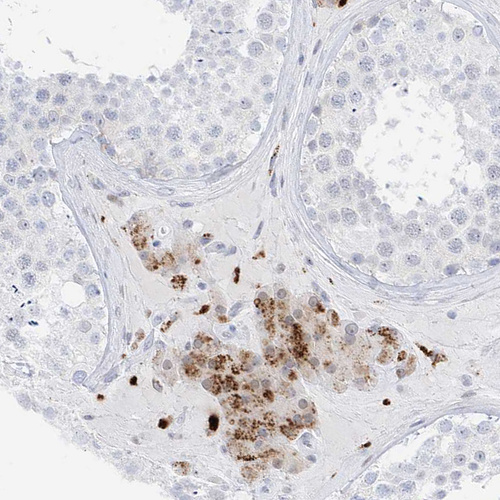

Immunohistochemical staining of human fallopian tube shows strong granular cytoplasmic positivity in glandular cells.